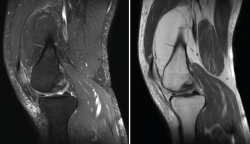

1.2.3. Ligamento cruzado posterior (LCP) (Figuras 45 y 46)

Figura 45. Corte de secuencia sagital T2 Fat-Sat de resonancia magnética: ligamento cruzado posterior normal.

Figura 46. Corte de secuencia sagital T2 Fat-Sat de resonancia magnética: rotura de ligamento cruzado posterior distal.

1.2.2. Ligamento cruzado anterior (LCA) (Figuras 40, 41, 42, 43 y 44)

Figura 40. Corte de secuencia sagital T2 Fat-Sat de resonancia magnética de rodilla: ligamento cruzado anterior normal.

Figura 41. Cortes de secuencia sagital T2 Fat-Sat de resonancia magnética de rodilla: rotura central del ligamento cruzado anterior.

Figura 42. Cortes de secuencia sagital T2 Fat-Sat: rotura proximal del ligamento cruzado anterior.

Figura 43. Corte sagital oblicuo T2 de resonancia magnética de rodilla: plastia del ligamento cruzado anterior íntegra.

Figura 44. Corte de secuencia sagital T2 Fat-Sat y T2 de resonancia magnética de rodilla: rotura de plastia del LCA.